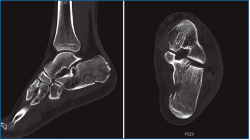

En las fracturas de calcáneo donde se afecta la articulación subastragalina posterior existe un trazo de fractura principal que separa 2 grandes fragmentos: el anteromedial “fijo” y el posterolateral, que se desplaza. Un segundo trazo de fractura ocasiona el hundimiento y la apertura de la subastragalina posterior. Sanders realizó una clasificación de estas lesiones intraarticulares basándose en la conminución y en las imágenes de tomografía computarizada (TC)(1).

Figura 1. Fractura del calcáneo Sanders IIA.

Figura 2. Fractura del calcáneo Sanders IIB.